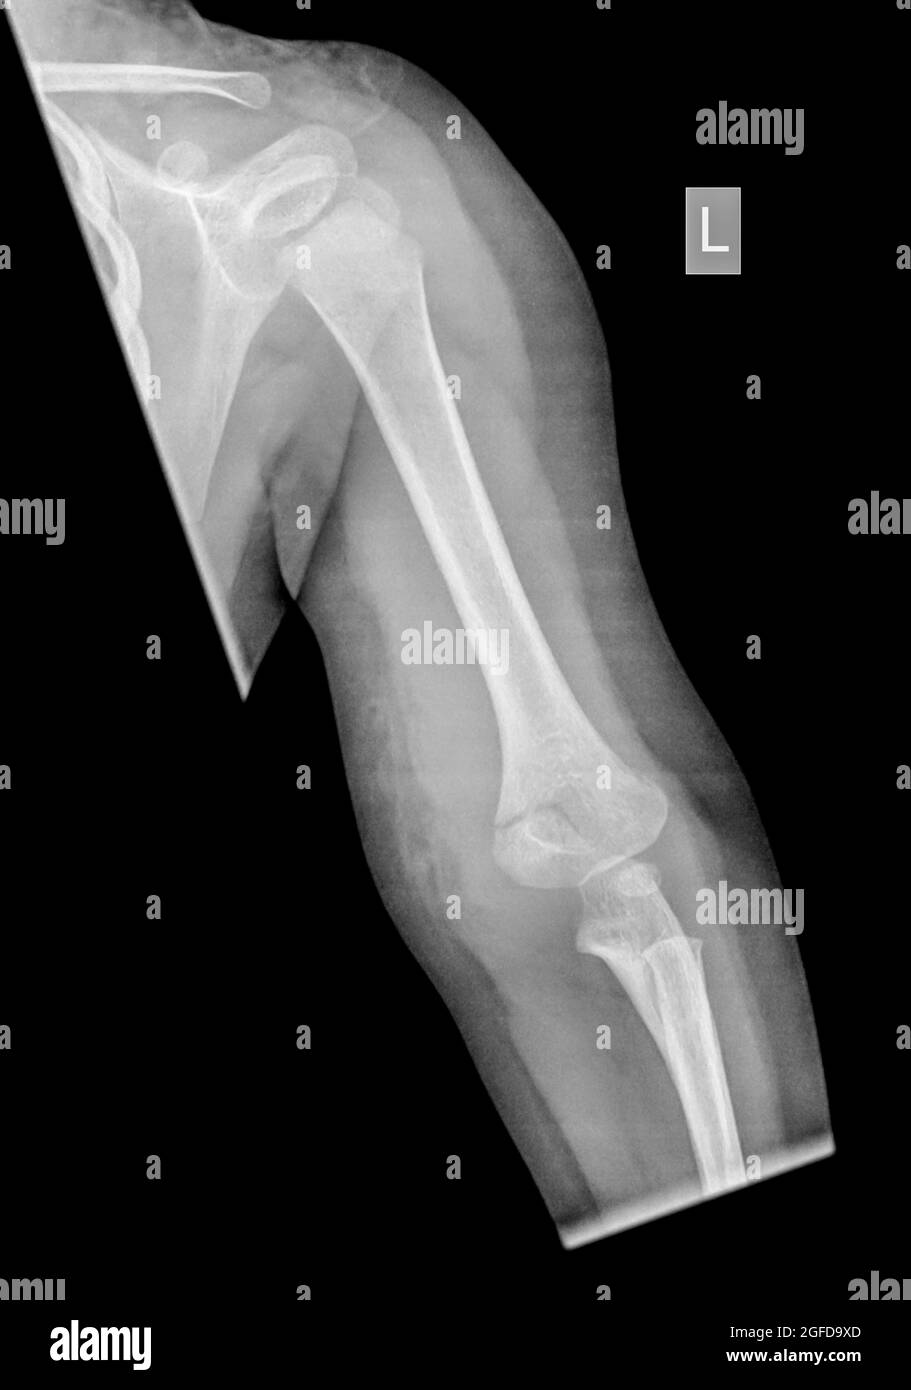

Il femore è una delle ossa più forti del corpo e una rottura o frattura nellosso del femore è spesso causata da lesioni gravi come traumi subiti in un incidente automobilistico. Quando la frattura è lungo il corpo del femore. Fratture del femore associate alluso a lungo termine dei bifosfonati.

Lultimo caso T148 è quello di una frattura sopracondilare di un femore sinistro con neoformazione ossea sulla superficie mediale. Il trattamento di una frattura del femore sopracondilare è altamente variabile e può comportare un cast o un tutore un fissatore esterno una verga intramidollare o luso. Frattura del ginocchio articolare distale La frattura del femore distale nota anche come frattura del femore sopracondilare si trova sullalbero vicino allarticolazione del ginocchio.

Questo è stato rivisto in un chiodo intramidollare e guarito senza incidenti a destra Frattura del femore distale bassa periprostetica sopra il ginocchio. Frattura di epifisi inferiore separazione 82123. Talvolta queste fratture si estendono nellarticolazione del ginocchio e separano la superficie dellosso in pochi o molte parti.

In questa forma di frattura del femore il frammento osseo superiore viene ruotato verso lesterno dalla muscolatura. Frattura del condilo femorale Esistono diversi tipi di lesione condilare. La frattura del femore sopracondilare interprotesico inizialmente trattata con una piastra laterale ha successivamente continuato a non unione e rottura della piastra a sinistra.

Notching intaccatura della corticale dorsale del femore frattura del femore sopracondilare. Complicanze elle ratture sovracondiloidee llomero i t diatrica Complication of upracondylar umeral ractures in hildren 260 1 F 2 tena 1 oto 1 O Ortopedia e Traumatologia 2 O irurgia iotruttia e della ano Itituto Giannina Galini Genoa. Una frattura del femore può causare un sanguinamento significativo che può causare shock.

Frattura del femore sopracondilare. FRATTURA DEL COLLO DEL FEMORE. Si noti la posizione della linea di frattura sulla corticale laterale e lispessimento corticale focale nel sito di frattura.

La frattura del ginocchio si può verificare nella rotula condili femorali piatto tibiale eminenza intercondiloidea tibiale e tuberosità tibiale. Una frattura del femore sopracondilare è una condizione problematica in quanto può aumentare il rischio di sviluppare lartrite del ginocchio più avanti nella vita. Quanto vale in termini di danno biologico un soggetto anziano investito sul marciapiede frattura di femore e di Colles che ha perso la capacità di deambulare.

La frattura più frequente al di sopra di TKR è rappresentata da una frattura di femore sopracondilare.